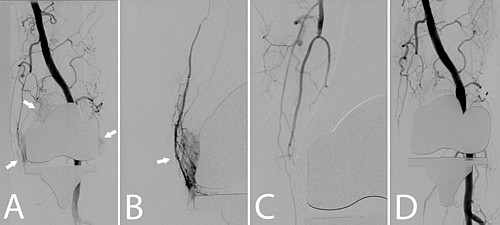

Nach einer lokalen Betäubung (Lokalanästhesie) in der Leiste wird ein kleiner Katheter in die Hauptschlagader des Beins (A. femoralis com.) eingebracht und am Beispiel des Kniegelenks zu den versorgenden Gefäßen vorgeführt. Die einzelnen kleinen Gefäße, welche das Kniegelenk versorgen werden gezielt (superselektiv) mittels eines Mikrokatheters (Durchmesser 0,51 mm) sondiert. Lässt sich eine Entzündungsreaktion durch eine vermehrte Kontrastmittelaufnahme („Blush“) beweisen, wird ein Medikament gespritzt, was die kleinsten Gefäße verschließt (Embolisation). Nach der Embolisation werden die Katheter wieder entfernt und die Punktionsstelle mittels manueller Kompression verschlossen. Eine Bettruhe von mindestens 6h und ein Druckverband für 24h sind nach dem Eingriff notwendig. Deshalb ist für Sie ein Krankenhausaufenthalt mit einer Übernachtung zu planen.